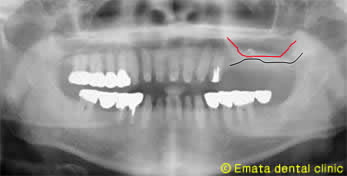

Before

左上奥には骨がなく歯周病が原因で抜歯になったのでしょう